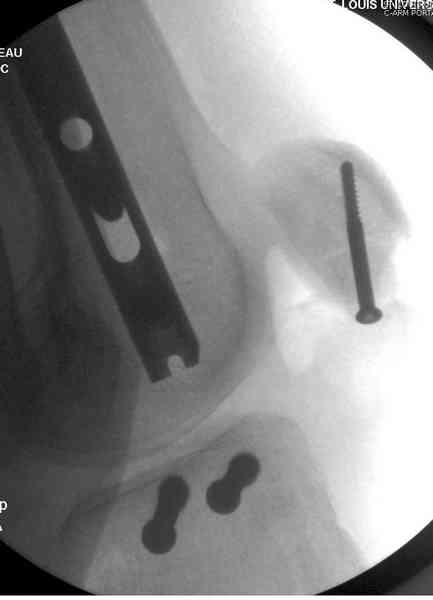

Пострадавшему 21 г., травма скоростная, после I&D с расширением раны, на бедре сделана операция ретроградным интрамедуллярным штифтом, остеосинтез с частичной резекцией надколенника и ушивание собственной связки.

На голень наружный фиксатор, рану на бедре ушили (рана была изнутри кнаружи всего 2 см). По протоколу травматических больных, до операции обследован ангиографически, (у больного дистально не смогли определить пульсацию) сосудистый хирург подтвердил проходимость на всем протяжении магистрального сосуда нижней конечности по снимкам ангиограмм.

В настоящее время больной в реанимации по поводу Черепно Мозговой Травмы и состояние улучшается. Запланировал ушивание раны в пятницу, если позволит состояние мягких тканей и при отсутстви отека возможно удастся просунуть перкутанно медиальную пластину.

КТ пилона имеем.